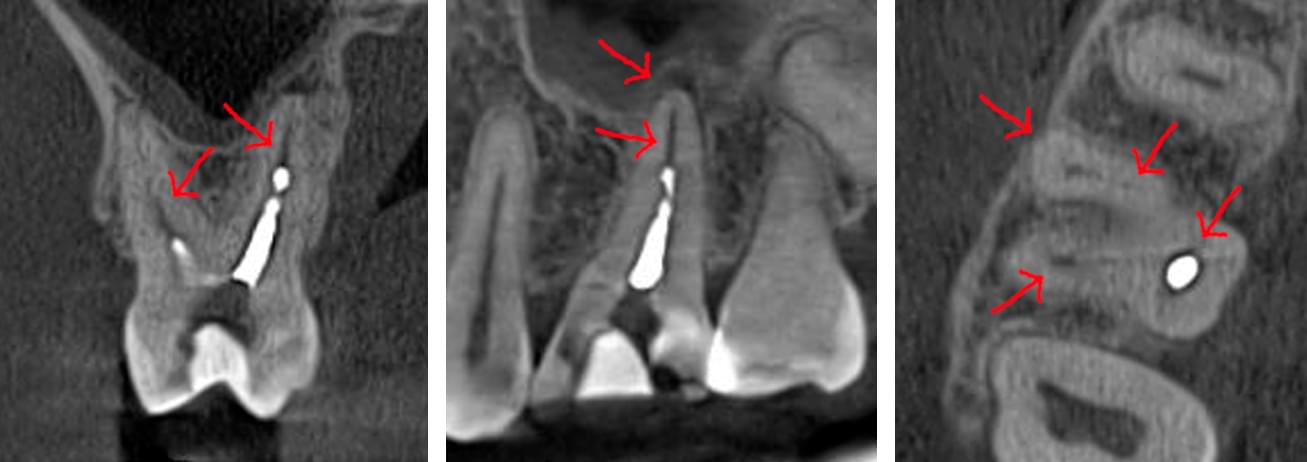

Головний недолік 2D-рентгену — це площинне зображення. Зуби, корені, щільна кістка та гайморові пазухи накладаються один на одного, створюючи «візуальний шум».

Зуб — це не просто монолітний об'єкт, а складна система мікроканалів. На плоскому 2D-знімку вони часто перекривають один одного, створюючи ілюзію простої анатомії.

Непомічений канал — це джерело майбутньої інфекції та причина «загадкового» болю після лікування. Завдяки високій роздільній здатності обладнання MyRay, лікар бачить кожен мікронний канал ще до того, як візьме до рук інструмент.

Коли коріння «ховає сюрпризи» - Корені зубів часто мають складну кривизну, гачкоподібні закручення або розгалуження, які на звичайному 2D-знімку накладаються один на одного, створюючи ілюзію прямого каналу. На плоскій картинці неможливо побачити реальний об'єм та напрямок вигину, що критично важливо при видаленні «зубів мудрості» або ендодонтичному лікуванні. КТ MyRay дає змогу лікарю заздалегідь побачити 3D-геометрію кожного кореня, оцінити його близькість до нижньощелепного нерва чи гайморової пазухи та підібрати правильну тактику роботи. Це мінімізує ризики поломки інструменту в каналі або травмування сусідніх структур, перетворюючи складну хірургію на прогнозовану процедуру.